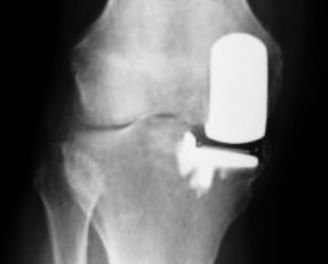

This is an example of a partial arthroplasty, where only one side of the knee joint has been replaced.

A total knee replacement replaces the whole articulation of femur and tibia - both sides - and very often the patella also. A partial knee replacement is indicated when the joint destruction affects only part of the joint. So, for example, the replacement may be of just one of the condyles of the femur and the part of the tibia it articulates with.